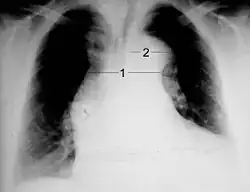

Stanford type B dissection of the descending part of the aorta (3), which starts from the left subclavian artery and extends to the abdominal aorta (4). The ascending aorta (1) and aortic arch (2) shown in the image are not involved in this condition.

Aortic dissection on CXR: Note is made of a wide aortic knob.

Chest radiography may although demonstrate a change in the morphology of the thoracic aorta which can be seen in aortic dissection. Classically, new widening of the mediastinum on radiograph is of moderate sensitivity for detecting an ascending aortic dissection; however, this finding is of low specificity, as many other conditions can cause apparent widening of the mediastinum.

There are several other associated radiographic findings:

• The "calcium sign" describes an apparent separation of the intimal calcification from the outer aortic margin by greater than 10 mm.

• Pleural effusions, more commonly in descending aortic dissections, and typically left-sided.

• Other: the obliteration of the aortic knob, depression of the left mainstem bronchus, loss of the paratracheal stripe, and tracheal deviation.

Importantly, about 12 to 20% of aortic dissections are not detectable by chest radiograph; therefore, a "normal" chest radiograph does not rule out aortic dissection. If there is high clinical suspicion, a more sensitive imaging test (CT angiogram, MR angiography, or transesophageal echo) may be warranted.